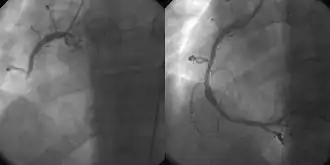

- Коронарная ангиография позволяет исследовать сердце после внутривенного введения контрастного вещества на основе йода через катетер, предварительно обследовав пациента на предмет противопоказаний к йоду. Ангиография может быть назначена после получения аномальных результатов ЭКГ и стресс-тестов, вместе с жалобами на боль и другими характерными симптомами[27][28].